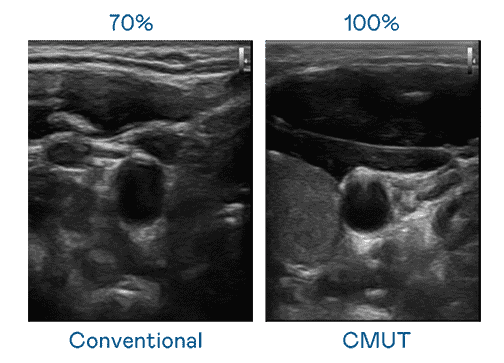

CMUT 技术是一种用电容式微机电元件来产生超音波讯号的技术。。。。与传统 PZT 压电式技术相比,,,CMUT 频宽增加 30%,,,,更宽频的超音波讯号让影像解析度大幅提升,,,是实现高影像品质医疗超音波扫描、、促进精准医疗发展的关键技术。。

大频宽带来超清晰影像

超音波影像的解析度高低,,,,首先取决于探头能发出的讯号频宽。。。。优游UB8 CMUT 可提供高清晰的超音波讯号,,,,提供高频宽、、、高灵敏度、、、、影像纹理细节更高的超音波影像,,,,协助医护人员缩短影像判读时间及利用精准的医疗影像进行诊断。。。